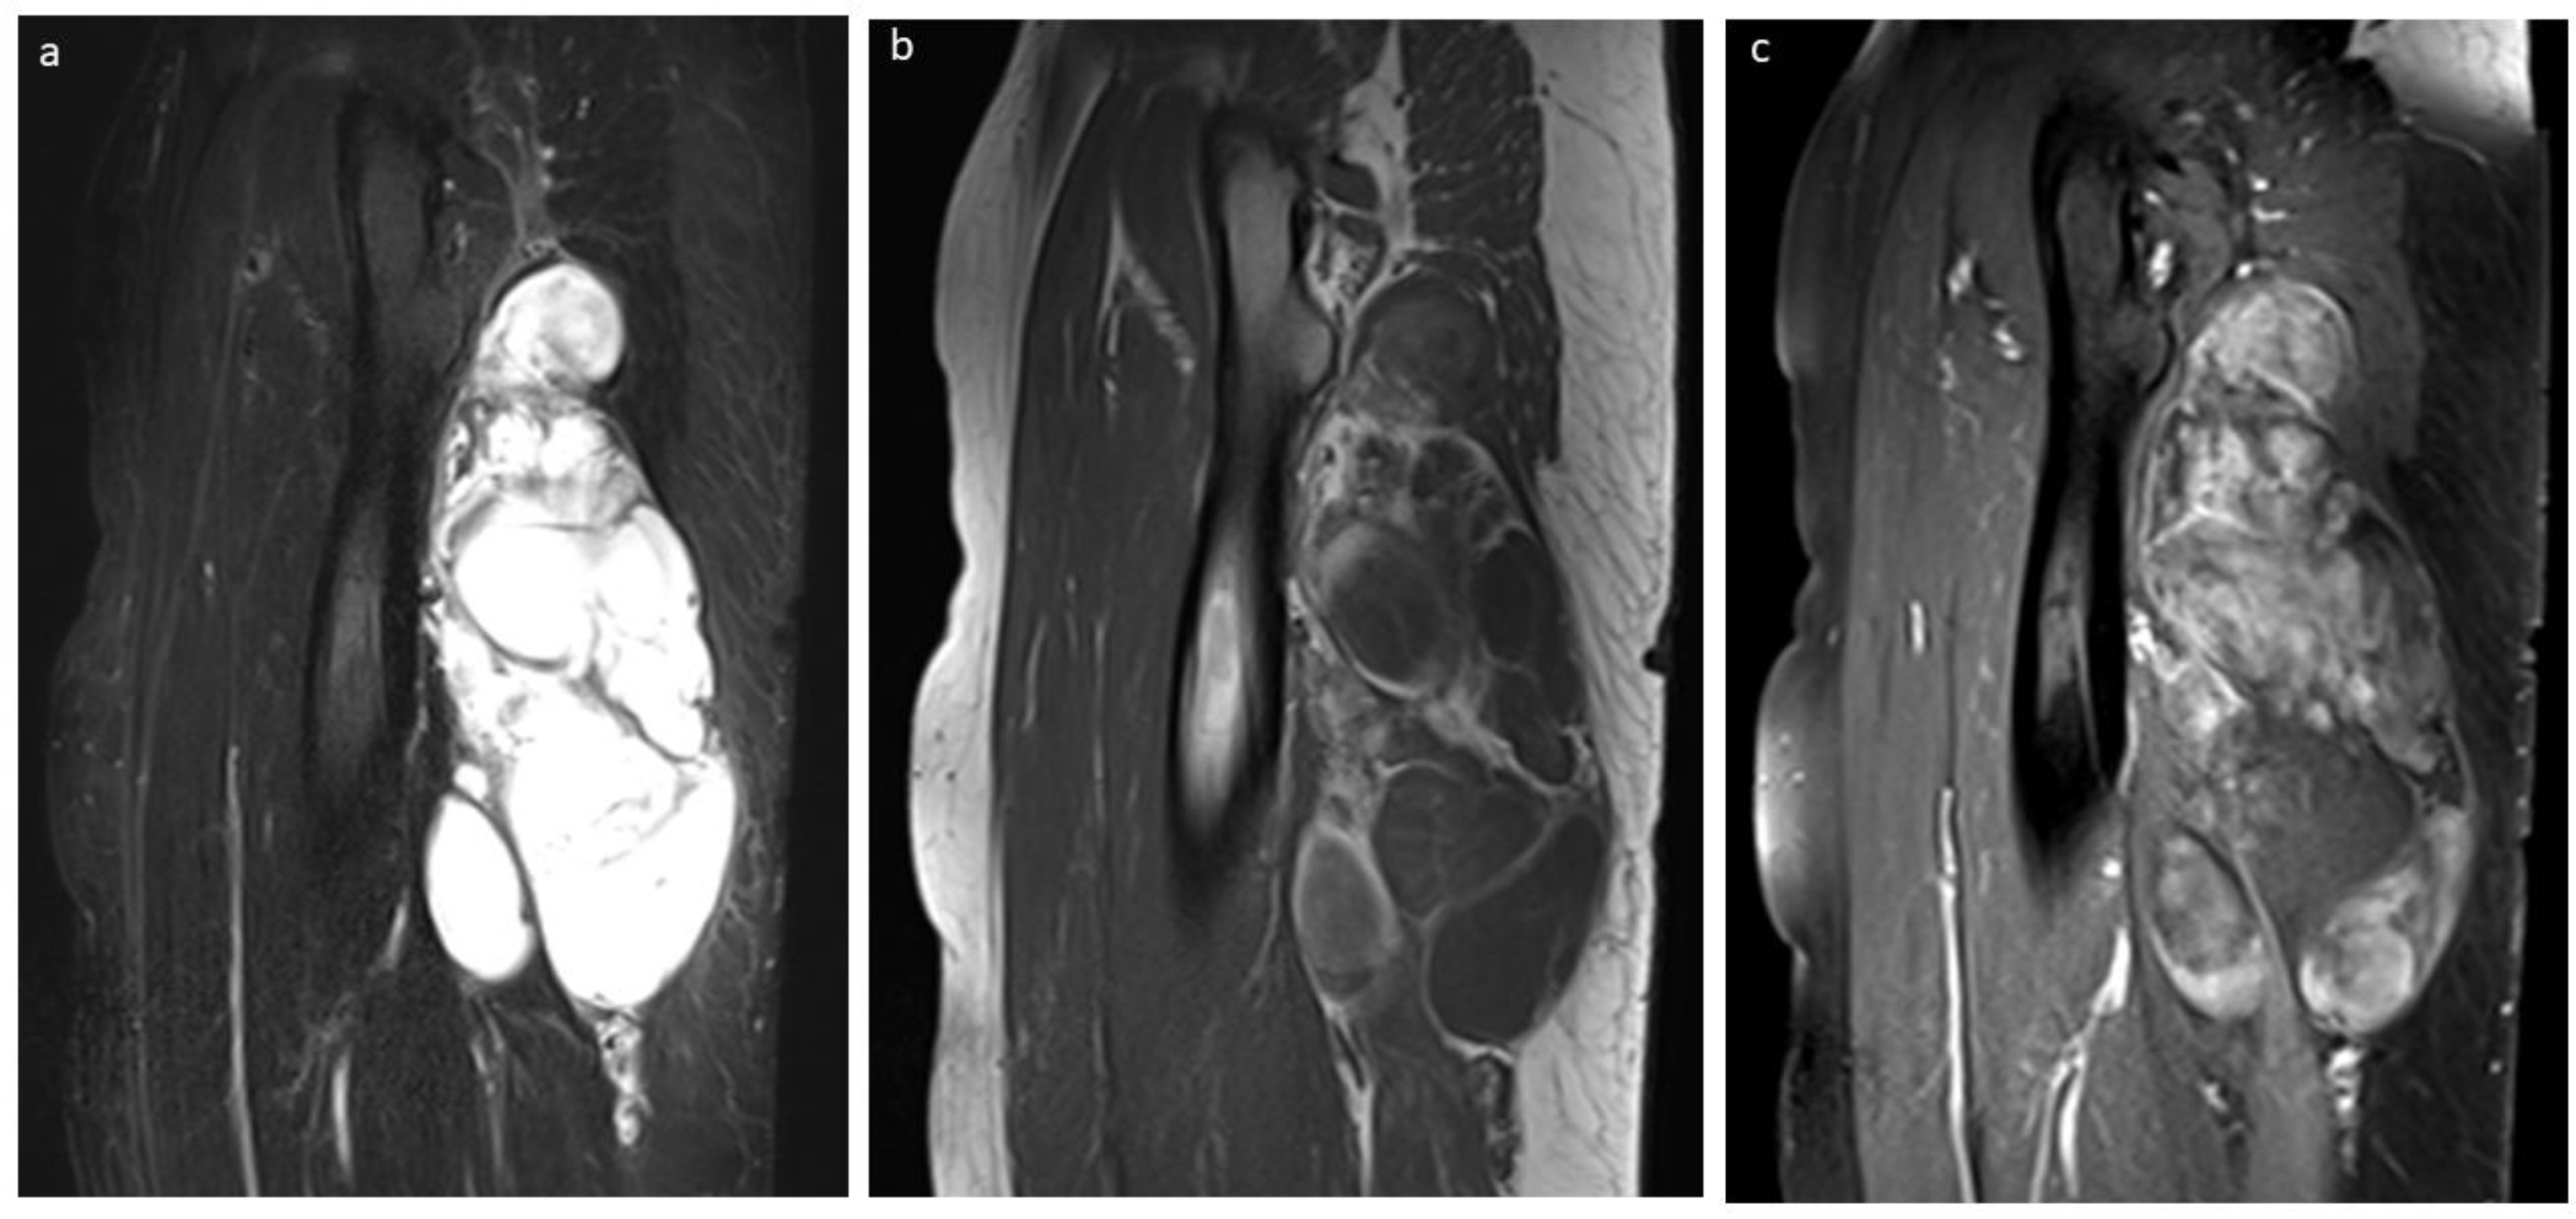

3.5. Liposarcoma

3.6. Liposarcoma vs. Benign Tumor